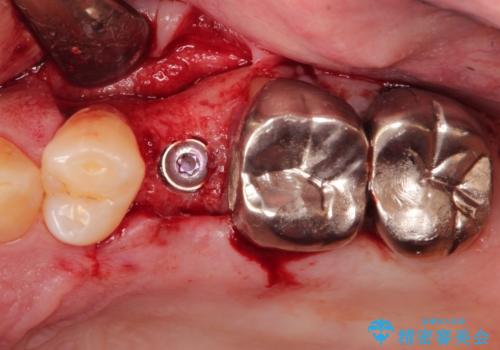

小臼歯部のインプラント

- 他院にて└5の治療を繰り返しても痛みがなくならないことを主訴に来院されました。

患歯はすでに2回の歯根切除術を受けており、長期的な予後不良となることから抜歯を選択されインプラントによる治療を行いました。

└6の不良補綴物も認め、根管治療及び補綴もやり替えてます。